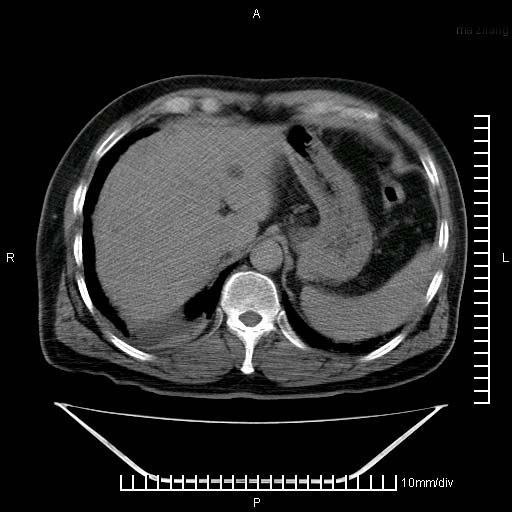

标题: CT25082:肝脏增强:男性,70岁 [打印本页]

标题: CT25082:肝脏增强:男性,70岁

患者以心脏疾病收住院,腹部无明显症状,b超查肝脏有占位。

牛眼征,中心坏死无强化,外缘强化,最外缘又见低密度,考虑转移,与脓肿鉴别

肝内多发转移瘤,右下肺炎症并少量胸水。胃壁增厚建议胃镜,胰尾部“病变”为肠管。

1)肝脏多发性转移瘤(不排除胰尾癌转移所致可能)。2)腹水。3)右侧少量胸腔积液。

ct25082 结果:转移瘤

外院mr结果:胰尾恶性占位。

肝多发低密度灶;轻度强化,较水密度高,考虑转移,不排除肝脓肿